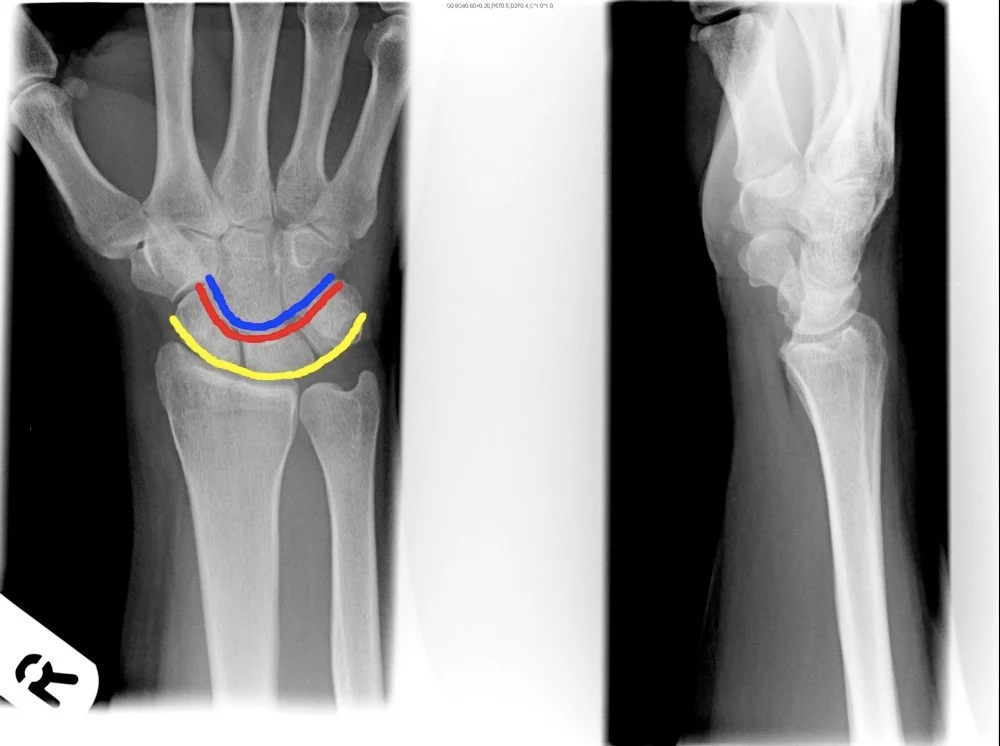

- x-ray of wrist undisplaced fracture of scaphoid

- In Trauma â âFollow the Cortexâ â adjust brightness/contrast to reveal the fracture line.

A 29âyearâold man fell from a ladder and presents with pain in the wrist.

- Site â wrist

- Type â (Specify fracture type)

- Fracture line â (Describe orientation)

- Displacements â (Note any displacement)

- Special issues â (Highlight any neurovascular or softâtissue concerns)

A 37-year old man fell from a down the stairs, C/O pain at wrist ⢠Site ⢠Type ⢠Fracture line

- Displacements

- Special issues

- Site

- Type

- Fracture line

- ⢠Site

- ⢠Type

- ⢠Fracture line

- ⢠Displacements

- ⢠Special issues